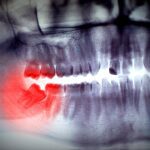

In practice though, a dentist can perform an x-ray to see if your wisdom teeth have one-third root formation. Whatever age this occurs makes it a good time for an extraction. The older you get, the greater the chance for complications, as the wisdom teeth will have more time to take root. Once the teeth grow to around two-thirds root formation, it makes them harder to remove and increases the risk of nerve injury.

Impacted Wisdom Teeth

Wisdom teeth that fail to erupt from the gum line end up trapped below it, becoming impacted. This creates a gap between the gum line and the teeth. If this occurs, not only is it quite painful, but it can also cause abscesses, infections, cavities, or even gum disease.